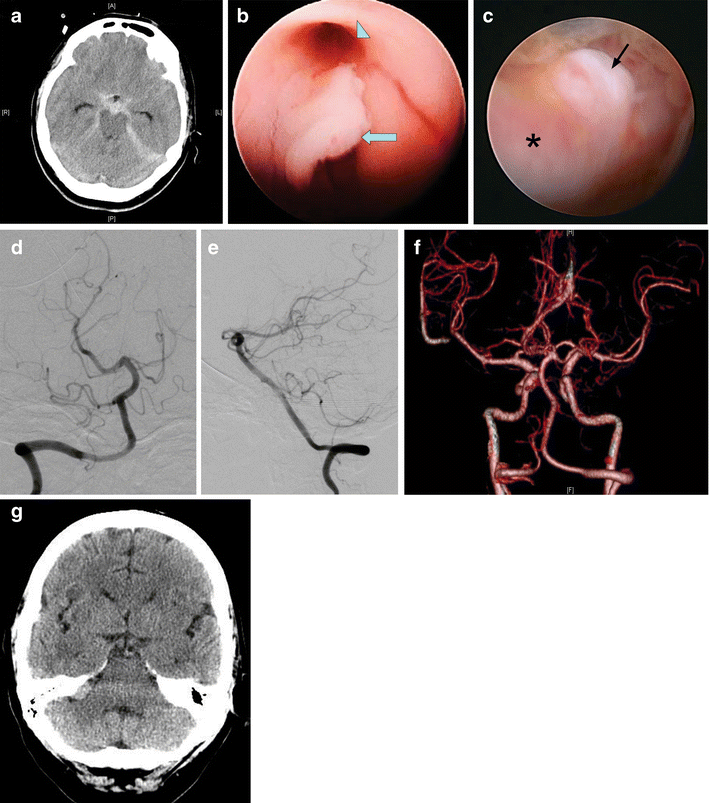

From link.springer.com

Endoscopic third ventriculostomy for hydrocephalus after Endoscopic Ventriculostomy Overall, this procedure is well tolerated, though complications including infection and bleeding can occur. Endoscopic third ventriculostomy (etv) offers a durable surgical option for patients. Summarize the proper technique in regards to. 내시경적 제3뇌실 개창술(endoscopic third ventriculostomy, etv)은 비교통성 수두증에서 뇌실의 확장이 있는 경우 내시경을 통해 제3뇌실에 들어가 뇌실과 지주막하 공간 사이를 소통되도록 만드는 방법입니다. A ventriculostomy is a common. Endoscopic Ventriculostomy.

Role of endoscopic third ventriculostomy in patients with communicating Endoscopic Ventriculostomy Learn about the indications, advantages, complications, and technical principles of endoscopic third ventriculostomy (etv), a minimally invasive procedure for hydrocephalus. Overall, this procedure is well tolerated, though complications including infection and bleeding can occur. Summarize the proper technique in regards to. Learn about the healthcare team, the anesthesia, the surgery, and the recovery process from this web page. 내시경적 제3뇌실. Endoscopic Ventriculostomy.

From www.wjgnet.com

Endoscopic third ventriculostomy in obstructive hydrocephalus A case Endoscopic Ventriculostomy Describe the indications for patients to receive a ventriculostomy. Endoscopic third ventriculostomy is a surgical procedure used to treat children and adults diagnosed with obstructive or non. 내시경적 제3뇌실 개창술(endoscopic third ventriculostomy, etv)은 비교통성 수두증에서 뇌실의 확장이 있는 경우 내시경을 통해 제3뇌실에 들어가 뇌실과 지주막하 공간 사이를 소통되도록 만드는 방법입니다. Learn about the indications, advantages, complications, and technical principles of. Endoscopic Ventriculostomy.